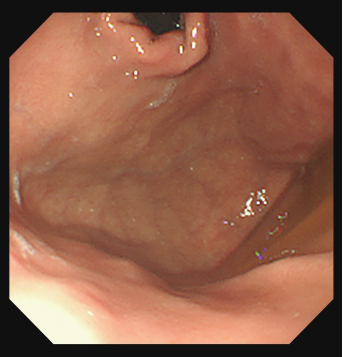

⑧静脉套扎及组织胶注射

肝硬化食管静脉曲张一旦破裂往往造成致命的大出血。内镜下食管静脉曲张套扎术(EVL)是对食管下段曲张静脉逐一结扎,使其缺血狭窄、静脉闭塞,增加静脉周围纤维覆盖,从而使曲张静脉消失,达到止血和预防再出血。

食管静脉曲张

食管静脉破裂出血

食管静脉曲张套扎进行中

食管静脉曲张套扎进行中近观

食管静脉曲张套扎恢复后

正常胃底

胃底静脉曲张

组织胶注射

组织胶注射后

EVL是抢救食管静脉曲张破裂大出血、预防再出血的首选方法,该技术具有快捷、简单、并发症少、疗效高的特点 。EVL是治疗食管静脉曲张的一种新技术和新方法,我院消化内科开展EVL 1O年,多位教授具有丰富临床经验,每年救治了无数肝硬化食管胃底静脉曲张破裂大出血患者生命。